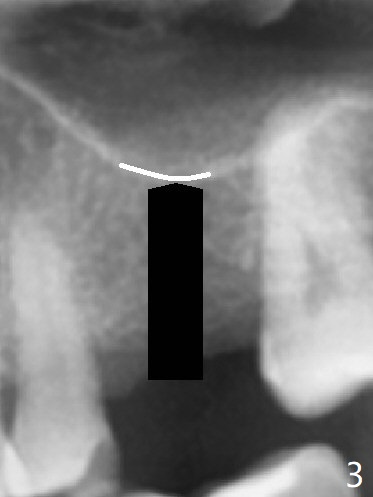

The guide is removed when the osteotomy at #14 (Fig.1 (8.45 mm bone height)) is finished in an under drilling manner in depth (Fig.2). The middle of the apical remaining bone is so thin (Fig.3 (white line representing the sinus floor)) that it can be pushed up like ping pong or eggshell (Fig.4 arrow). A 5x8.5 mm implant is placed with satisfactory insertion torque and depth, followed by insertion of a 6x3 mm healing abutment (Fig.5). There is mild resorption of the sinus floor distally 3.5 months postop, although the implant remains stable (Fig.6).